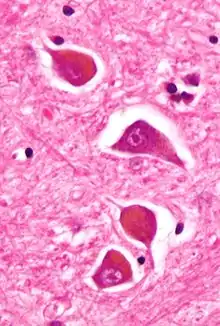

Micrograph of Alzheimer type II astrocytes, as may be seen in hepatic encephalopathy

The diagnosis of hepatic encephalopathy can only be made in the presence of confirmed liver disease (types A and C) or a portosystemic shunt (type B), as its symptoms are similar to those encountered in other encephalopathies. To make the distinction, abnormal liver function tests and/or ultrasound suggesting liver disease are required, and ideally a liver biopsy.[4][8] The symptoms of hepatic encephalopathy may also arise from other conditions, such as bleeding in the brain and seizures (both of which are more common in chronic liver disease). A CT scan of the brain may be required to exclude bleeding in the brain, and if seizure activity is suspected an electroencephalograph (EEG) study may be performed.[4] Rarer mimics of encephalopathy are meningitis, encephalitis, Wernicke's encephalopathy and Wilson's disease; these may be suspected on clinical grounds and confirmed with investigations.[8][15]

The diagnosis of hepatic encephalopathy is a clinical one, once other causes for confusion or coma have been excluded; no test fully diagnoses or excludes it. Serum ammonia levels are elevated in 90% of people, but not all hyperammonaemia (high ammonia levels in the blood) is associated with encephalopathy.[4][8] A CT scan of the brain usually shows no abnormality except in stage IV encephalopathy, when brain swelling (cerebral oedema) may be visible.[8] Other neuroimaging modalities, such as magnetic resonance imaging (MRI), are not currently regarded as useful, although they may show abnormalities.[15] Electroencephalography shows no clear abnormalities in stage 0, even if minimal HE is present; in stages I, II and III there are triphasic waves over the frontal lobes that oscillate at 5 Hz, and in stage IV there is slow delta wave activity.[4] However, the changes in EEG are not typical enough to be useful in distinguishing hepatic encephalopathy from other conditions.[15]